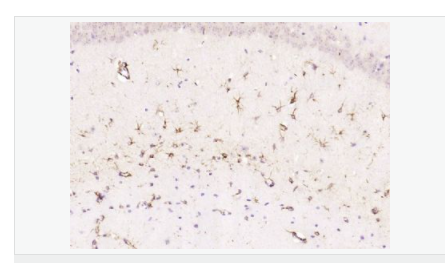

| 产品应用 | WB=1:500-2000 ELISA=1:5000-10000 IHC-P=1:200-1000 IHC-F=1:200-1000 Flow-Cyt=1μg/Test ICC=1:100 IF=1:200-800 (石蜡切片需做抗原修复) not yet tested in other applications. optimal dilutions/concentrations should be determined by the end user. |

| 产品介绍 | This gene encodes one of the major intermediate filament proteins of mature astrocytes. It is used as a marker to distinguish astrocytes from other glial cells during development. Mutations in this gene cause Alexander disease, a rare disorder of astrocytes in the central nervous system. Alternative splicing results in multiple transcript variants encoding distinct isoforms. [provided by RefSeq, Oct 2008] Function: GFAP, a class-III intermediate filament, is a cell-specific marker that, during the development of the central nervous system, distinguishes astrocytes from other glial cells. Subunit: Interacts with SYNM. Isoform 3 interacts with PSEN1 (via N-terminus). Subcellular Location: Cytoplasm. Note=Associated with intermediate filaments. Tissue Specificity: Expressed in cells lacking fibronectin. Post-translational modifications: Phosphorylated by PKN1. DISEASE: Defects in GFAP are a cause of Alexander disease (ALEXD) [MIM:203450]. Alexander disease is a rare disorder of the central nervous system. It is a progressive leukoencephalopathy whose hallmark is the widespread accumulation of Rosenthal fibers which are cytoplasmic inclusions in astrocytes. The most common form affects infants and young children, and is characterized by progressive failure of central myelination, usually leading to death usually within the first decade. Infants with Alexander disease develop a leukoencephalopathy with macrocephaly, seizures, and psychomotor retardation. Patients with juvenile or adult forms typically experience ataxia, bulbar signs and spasticity, and a more slowly progressive course. Similarity: Belongs to the intermediate filament family. SWISS: P14136 Gene ID: 2670 Database links: Entrez Gene: 2670 Human Entrez Gene: 14580 Mouse Omim: 137780 Human SwissProt: P14136 Human SwissProt: P03995 Mouse Important Note: This product as supplied is intended for research use only, not for use in human, therapeutic or diagnostic applications. 星形胶质细胞标志物 (Astrocyte Marker) GFAP是一个56kDa的中间丝蛋白(intermediate filament,IF),在中枢神经系统发育期是一个特异性的标志物,以区别星形细胞和其它胶质细胞。GFAP表达在皮层和海马,急、慢性皮质酮治疗时表达减少。 GFAP可以和人、大鼠、小鼠的GFAP反应,在正常和肿瘤性的星形胶质细胞阳性表达,而神经节细胞、神经元、成纤维细胞、少突胶质细胞和这些细胞来源的肿瘤细胞阴性表达,主要用于星形胶质瘤等中枢神经系统肿瘤的诊断和鉴别诊断,GFAP的缺乏可导致AD病。 |